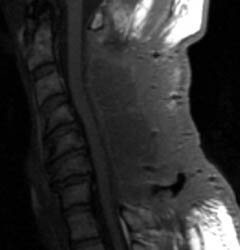

46 y.o. male, initial complaint of progressed with myelopathy,

difficulty walking, and imbalance. Underwent laminectomy C3 to C7, 2 months

prior to these images. Worsening numbness and weakness brought patient to seek

neurosurgical consultation again, prompting repeat imaging.

| Sagittal T1 pre (A) and post contrast

(B), sagittal T2 (C) and Axial T1 post contrast (D) MRI images

of the cervical spine demonstrating a large posterior fluid collection with an

obvious sinus tract inferiorly and associated gas bubbles. This was proved to be

a post-operative seroma and epidural scar (note the thick rind of enhancement)

that was partially accounting for this patient's residual and worsening symptoms

despite the initial decompressive surgery. |